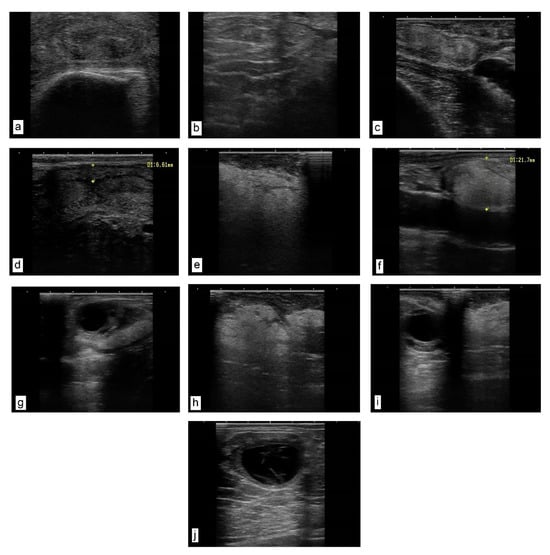

A transrectal ultrasound examination of the genital tract in both the heifers and cows in puerperium—in comparison with physiological aspects of the uterus and cervix (Figure 1a,c,d)—showed a diffuse, pathological hyperechogenicity of the cervical folds, suggesting lipid infiltration, as well as the proliferation of endocervical folds (Figure 1b) and the presence of paracervical hyperechoic (fatty) (Figure 1e) and parasalpingian formations (Figure 1f). This explains the change in the topography of the salpinx and the impossibility of oocyte retrieval, as well as the presence of intrauterine (Figure 1h) and paraovarian (Figure 1i) lipogranulomas. In cows in oestrus, the periovarian area shows a uniform marbled halo with a fatty appearance (Figure 1g). In the heifers, 14 days after oestrus, lutein ovarian cysts were found, with a wall thickness of approximately 3 mm and a hypoechoic area with septa inside (Figure 1j).

Figure 1.

Ultrasound images of the genital tract. Transrectal linear probe, 7.5 MHz. (a) Heifer cervix, cross-section near the involute flower. The folds of the cervical mucosa have a relatively uniform, denser, hyperechoic texture. (b) Cow cervix with proliferation of endocervical folds and their densification. (c,d) Uterine wall of a cow in puerperium. Normal uterus as an echogenic structure with the presence of a characteristic lumen. (e–i) Cow in puerperium. (e) Hypoechoic (fatty) formation, located paracervically. (f) Hypoechoic formation located parasalpingially, adherent to the serosa (longitudinal section) (size 21.7 mm). (g) Reactive cow ovary (with dominant follicle). The periovarian area presents a uniform marbled halo with a fatty appearance. (h) Sixty days postpartum. Uterine formation, amorphous, homogeneous texture with several areas of densification. (i) Reactive ovary with dominant follicle and parasalpingian formation on ligament (meso-ovary), uniform pixelated fatty appearance. (j) Heifer ovary 14 days after oestrus. Luteinic ovarian cyst, and a hypoechoic area with septa inside.